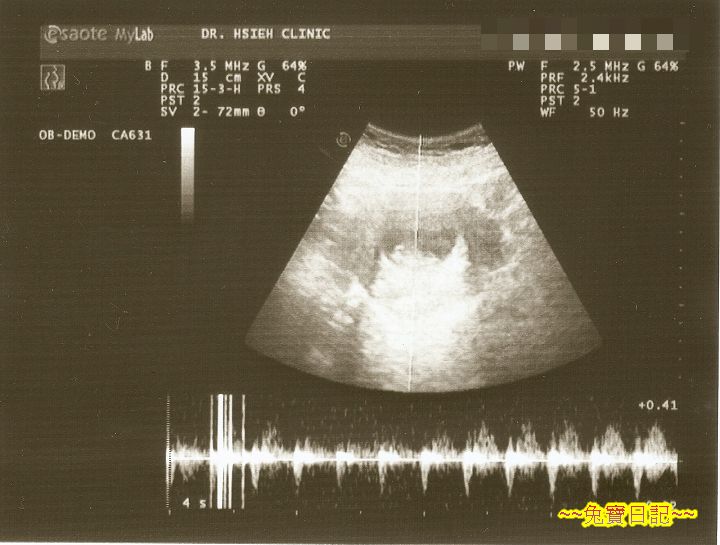

接著醫師好像換了個模式, 從超音波的儀器裡, 傳來一陣陣奇怪的聲音, 在一陣陣的雜音中, 偶爾會傳來幾聲咚咚的聲音. 這時候 A 意會過來, 醫生在量胎兒的心跳. 可是...

碰碰碰碰碰碰碰碰碰碰碰碰碰碰碰碰碰碰碰碰碰碰碰...

一陣強而有力, 規律不斷的拍擊聲傳了出來! 不過是很單純很規律的聲音罷了, 可是聽在 A 的耳朵裡, 直覺如聆仙樂, 悅耳動聽讓人感動!

這時醫生說話了, 胎兒一切正常, 心跳約每分鐘 140 下, 身長約 3 公分, 很正常感覺也很健康. 暫時不用擔心.